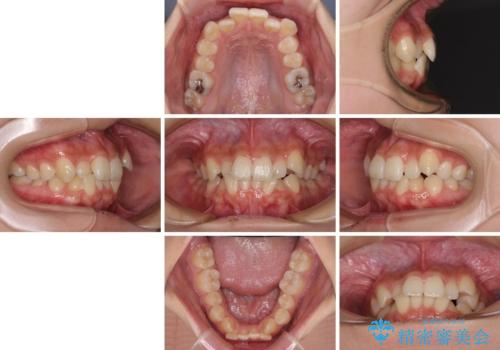

- 上下前歯のデコボコと八重歯を気にして来院された患者様です。

叢生を解消する際に出っ歯とならないようにするために、上下左右の小臼歯計4本を抜歯することとしました。

奥歯の咬み合わせが理想的であり、歯の移動に時間のかかる出っ歯でもなかったため、2年程度で治療を終えることを目標としましたが、無事に予定通りの2年間で終えることができました。